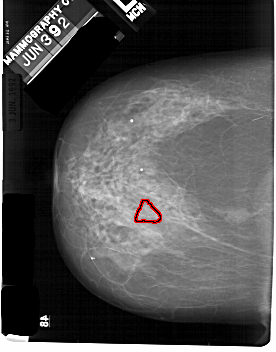

FILE: A_1824_1.LEFT_CC.OVERLAY

TOTAL_ABNORMALITIES 1

ABNORMALITY 1

LESION_TYPE CALCIFICATION TYPE PLEOMORPHIC DISTRIBUTION SEGMENTAL

ASSESSMENT 4

SUBTLETY 3

PATHOLOGY MALIGNANT

TOTAL_OUTLINES 1

BOUNDARY